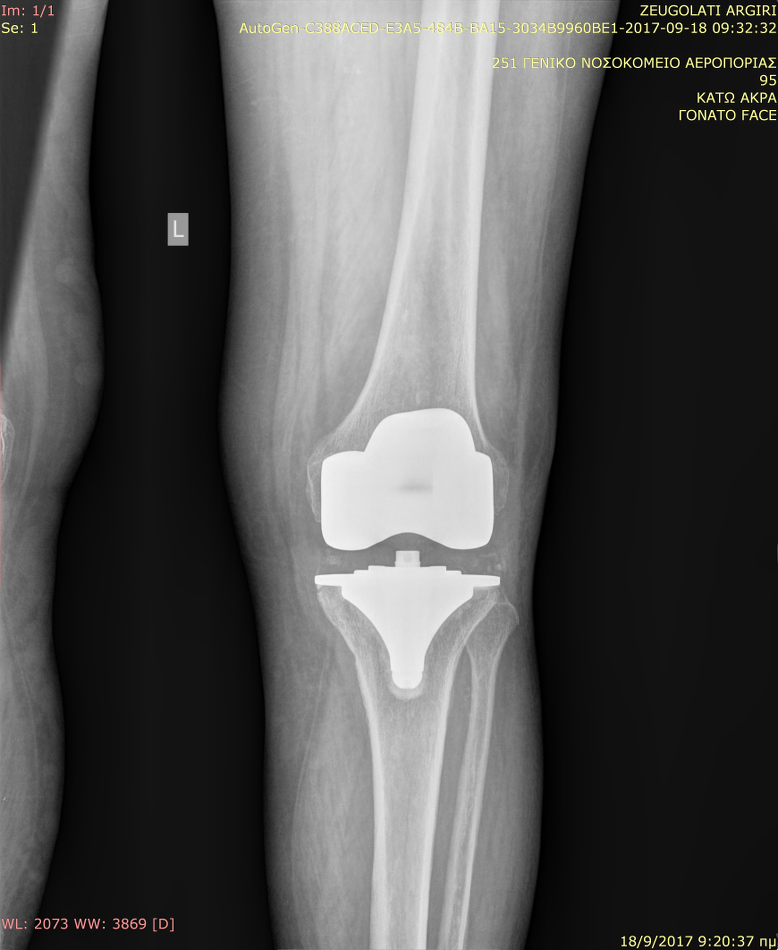

Αρθροπλαστικη γονατος

Γυναίκα 75 ετών με αρθρίτιδα γόνατος. Η ασθενής παρουσίαζε άλγος κατά την καθημερινή της δραστηριότητα. Υποβλήθηκε σε ολική αρθροπλαστική γόνατος επιφανείας, με διατήρηση του οπισθίου χιαστού συνδέσμου.